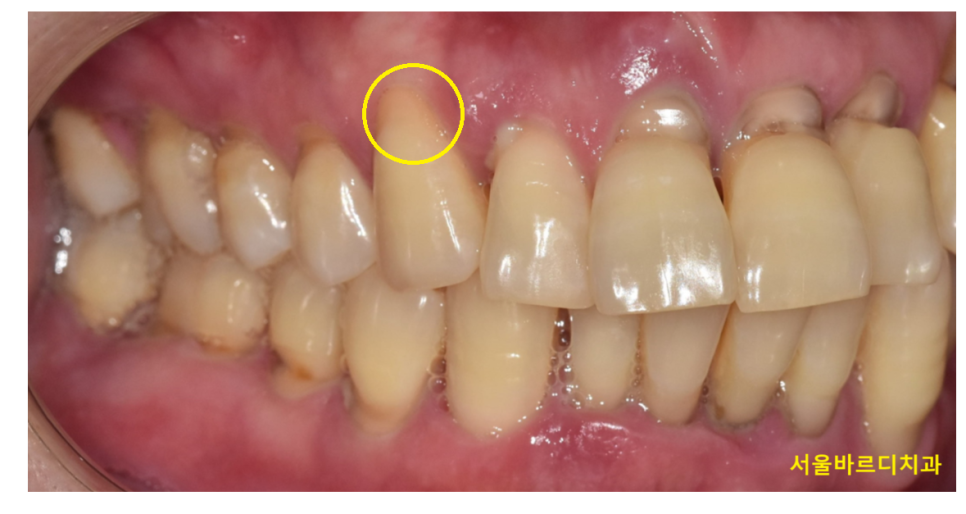

250417 레진 재료로 앞니를 떼워주었습니다 .

눈에 잘 보이는 앞니의 경우 심미성이 뛰어난 레진으로 보통 치료해줍니다.

내 치아와 색상 차이가 나지 않고

본드로 치아에 접착해주기 때문에 쉽게 떨어지지 않습니다.